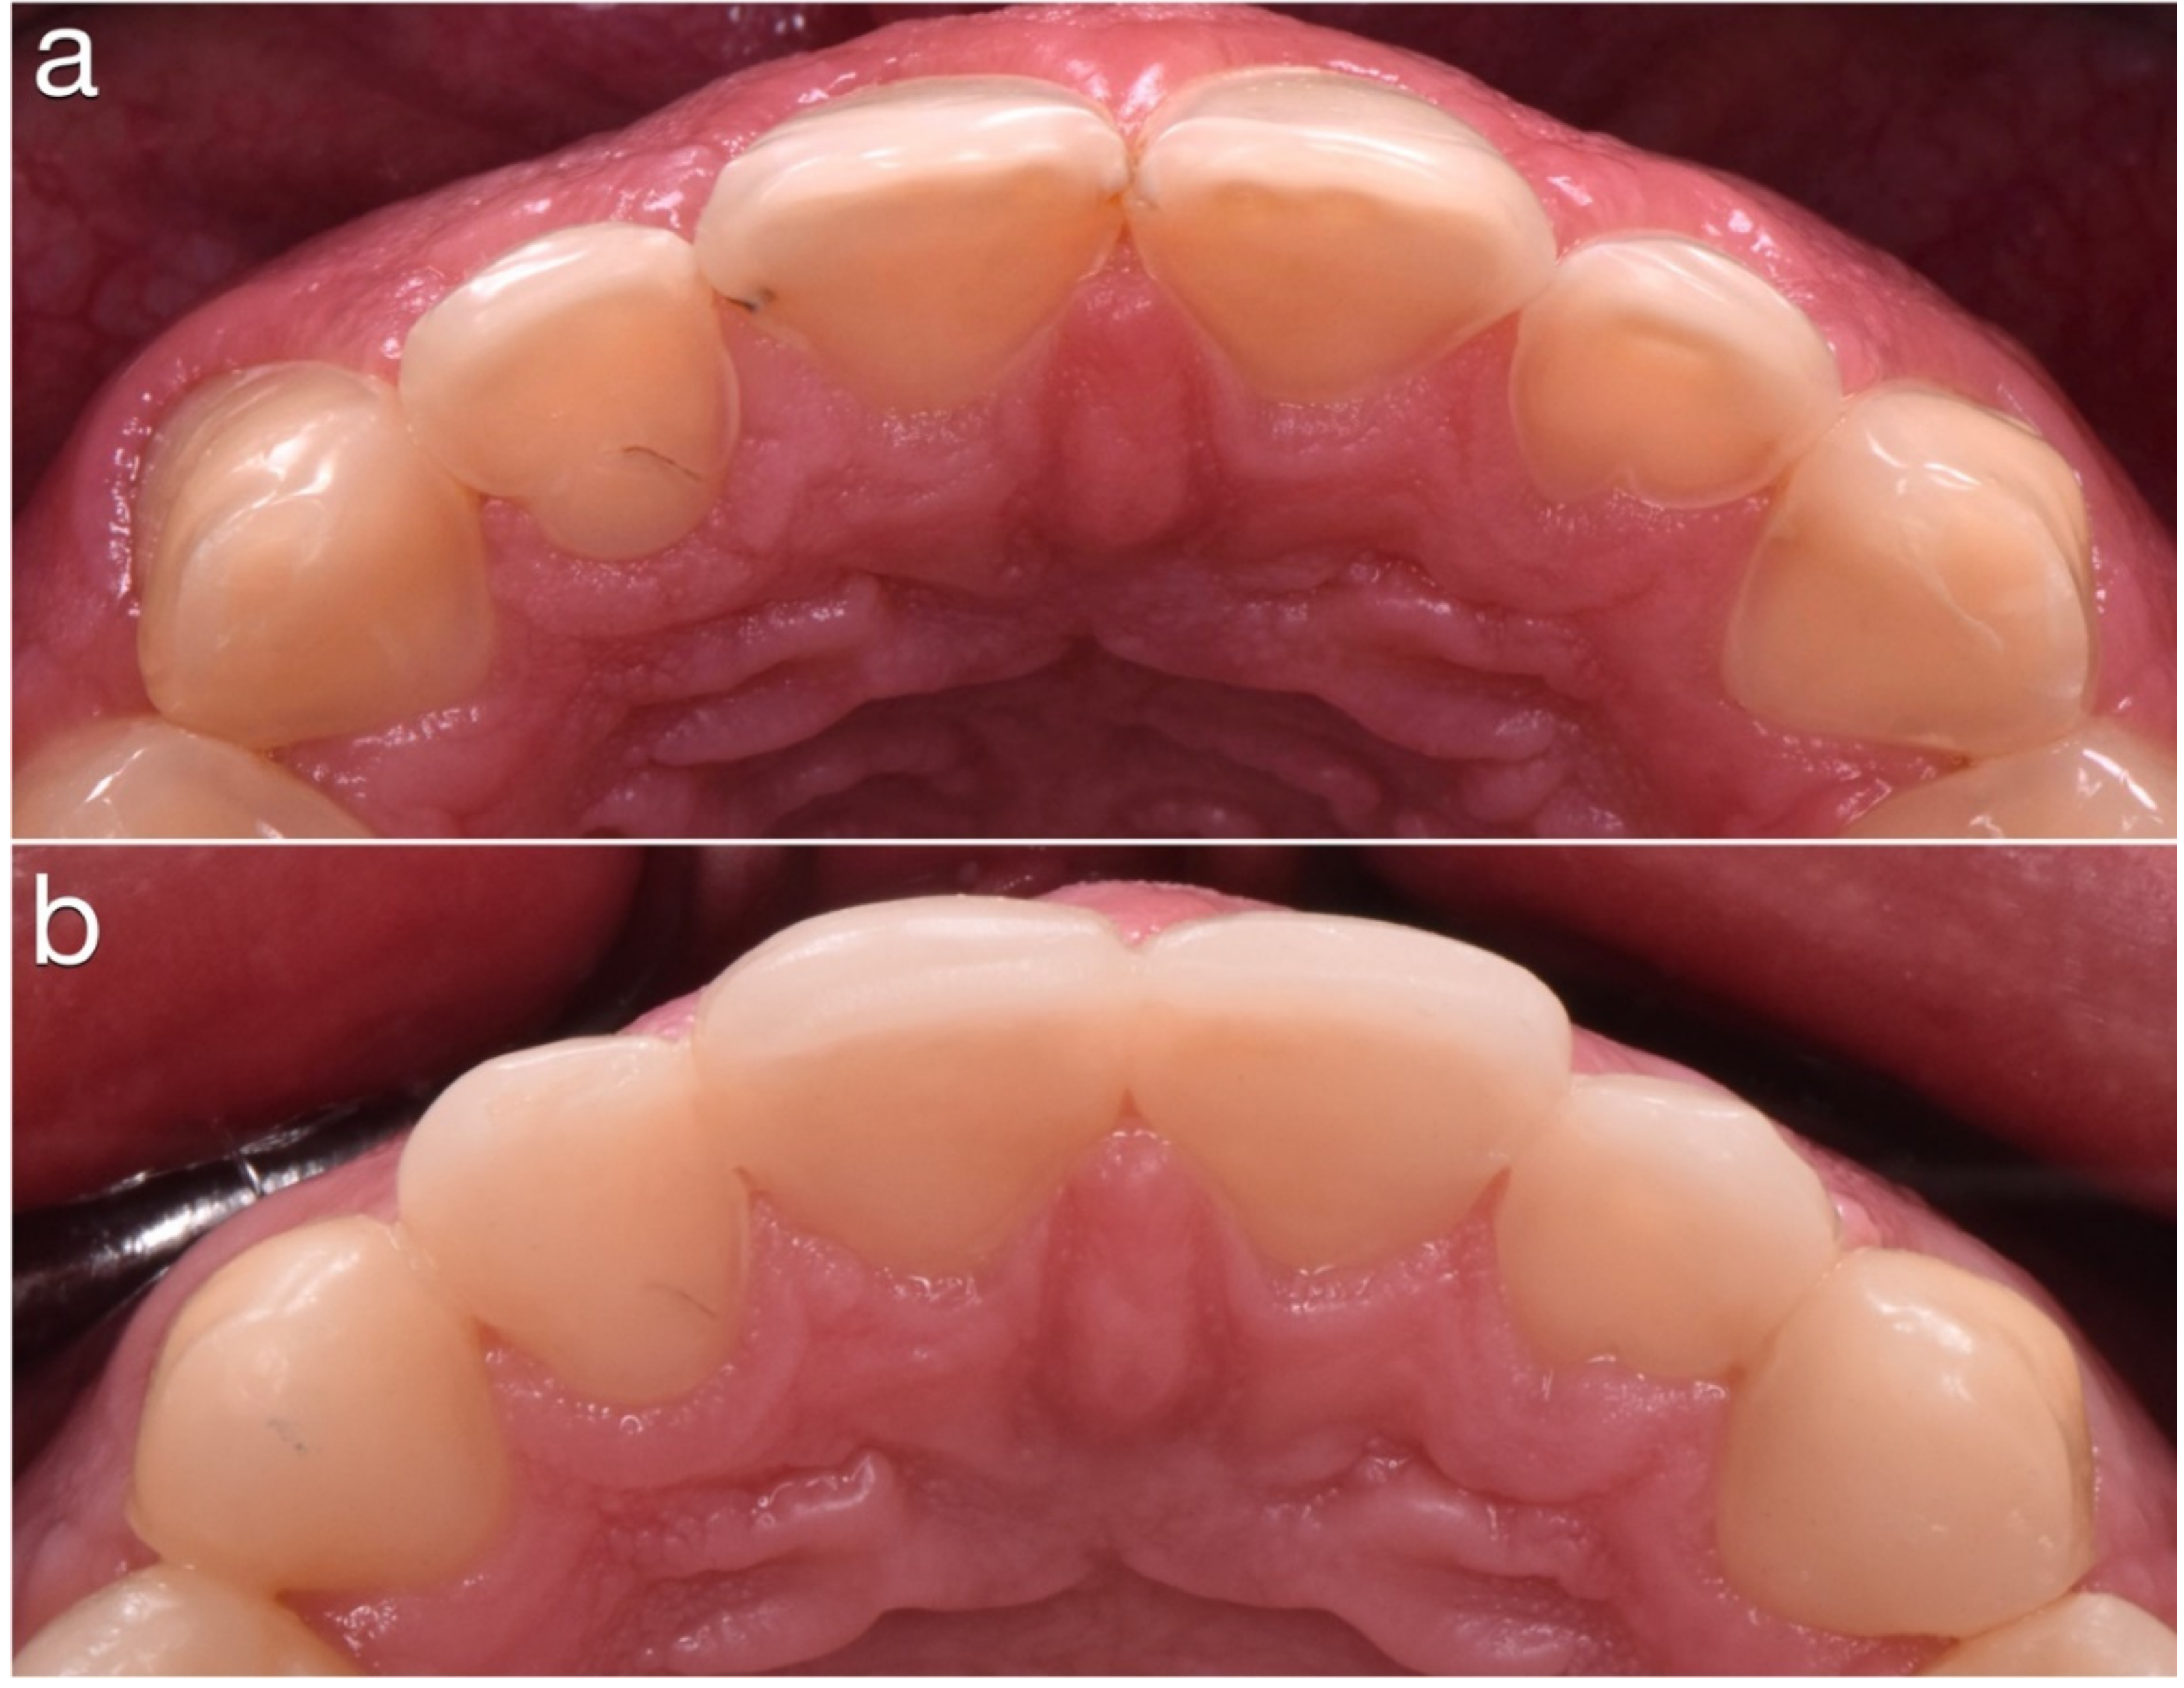

2.2. Restorative Phase